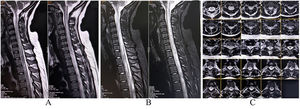

A complete blood cell count and metabolic profile were only remarkable for chronic disease anemia and raised erythrocyte sedimentation rate. Biopsy revealed non-small cell lung carcinoma. A chest X-ray revealed a left upper lobe lung mass. MRI of the brain and spinal cord revealed extensive transverse myelitis extending from C4 to D1 level (Fig. 7A, B, C). A nerve conduction study revealed an asymmetric sensorimotor axonal neuropathy with sensory ganglionopathy. A contrast-enhanced CT scan of the thorax and abdomen revealed no metastatic lesion. The paraneoplastic profile (serum and CSF) revealed high titers for anti-Ma2 antibody in serum, confirming it to be paraneoplastic myeloneuropathy. The patient and her caregivers refused any further treatment and took the patient home against medical advice (it is not a rare occurrence in Indian rural setups).